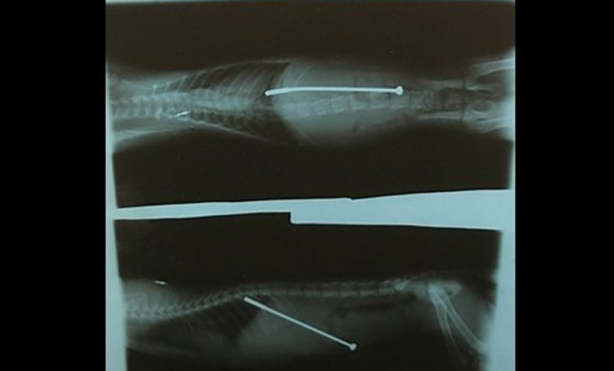

İsidro Mejia adlı Los Angeles'ta yaşayan bir inşaat işçisi geçirdiği kazayla ölümden döndü. Bir anlık dikkatsizlik sonucu makinadan fırlayan tam altı çivi kafatası ve boynuna saplandı.

#44